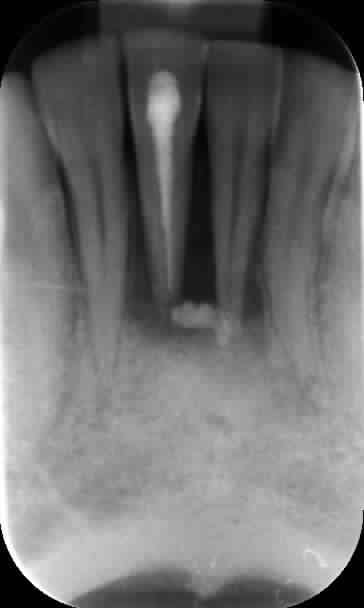

Quand même, un petit cas sympa endo-paro avec mobilités et fistule. Aujourd'hui, tout va bien : plus aucune sensibilité ni mobilité.

20/03/13, 24/04/13, 04/06/14